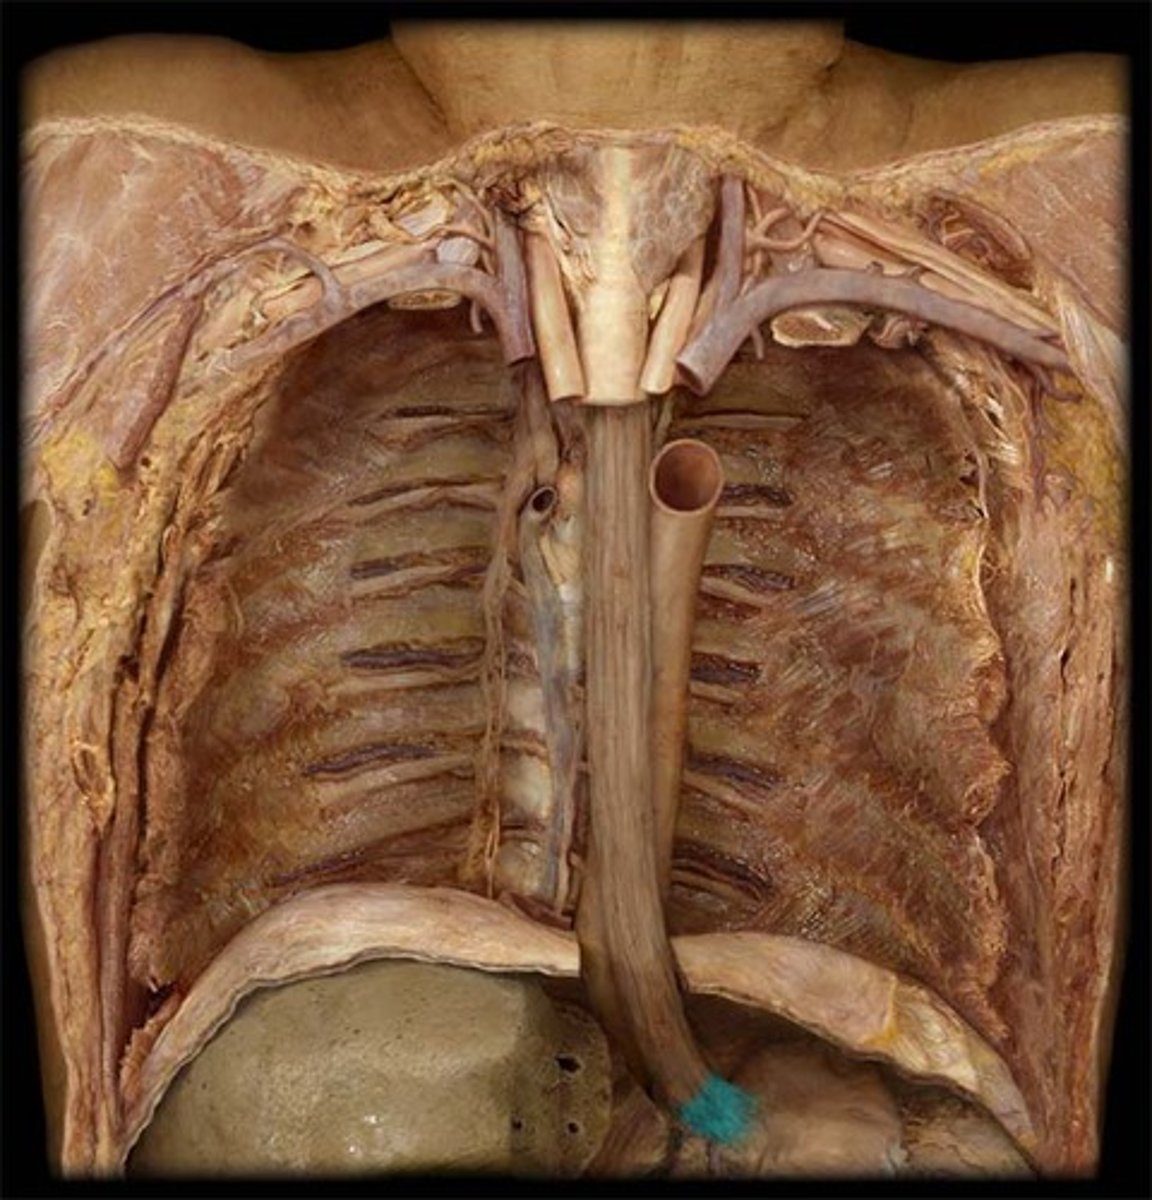

abdominal esophagus

inferior vena cava